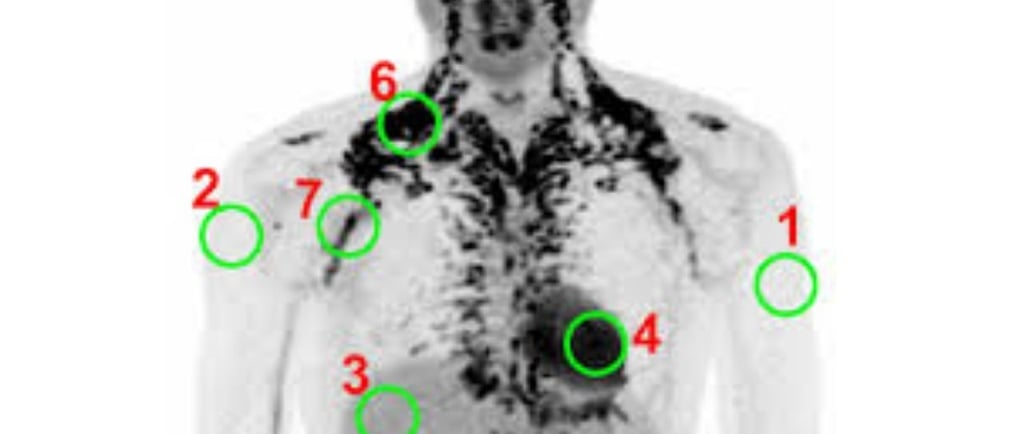

The ¹⁸F-FDG PET-CT scan has been a common method for assessing BAT.

When BAT is active, it uses up glucose, which is marked by the radioactive FDG tracer to show where the BAT is.

1. Xenon-Enhanced CT (Xe-CT): A More Accurate Option

Xenon-Enhanced CT is a big jump forward.

Recent studies that compared it directly with PET/CT suggest that Xe-CT could be more accurate for measuring BAT.

Since BAT has many blood vessels, it absorbs inhaled xenon gas rapidly.

This provides a strong signal that measures how well the tissue is functioning.